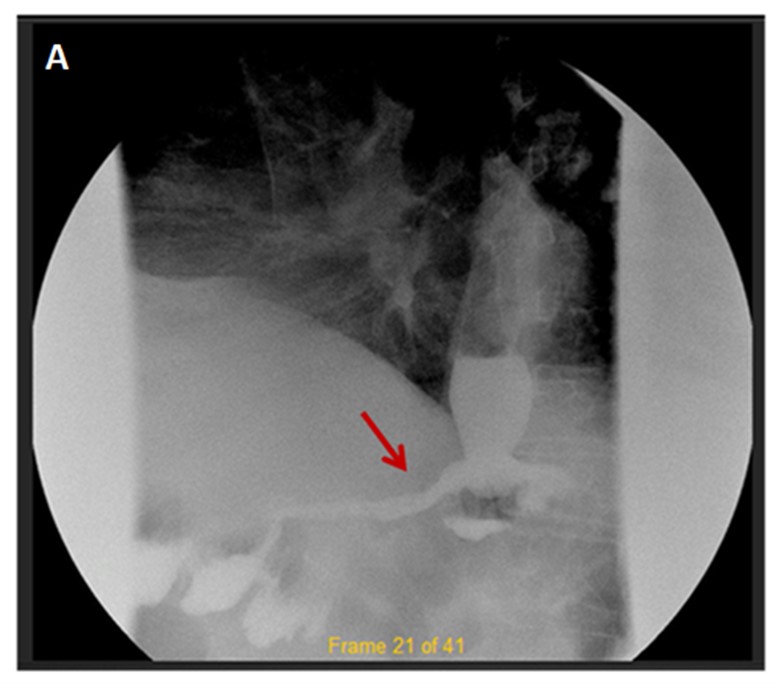

A 57-year-old male with a medical history of diabetes mellitus and morbid obesity underwent a Roux-en-Y gastric bypass surgery. The patient manifested a staple-line anastomotic leakage. After one week of conservative management, a 1.5cm persistent leakage was confirmed both radiologically (Figure A) and endoscopically (Figure B), so an endoscopic closure with over the scope clip (OTSC) using the suction method was performed (Figure C). Leakage of gastric liquids stopped after OTSC closure. No recurrence of the leakage was observed during the 12-month follow-up.